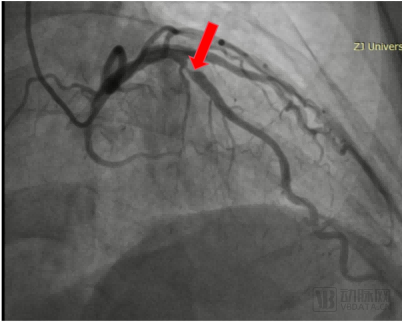

术前造影显示,患者前降支(LAD)中段,病变直径3.50mm,长度12mm,狭窄程度90%,TIMI血流3级。经王建安院士团队评估,决定采用冠脉血管重塑导管治疗患者LAD。

患者LAD术前造影